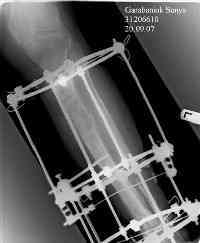

Владимир, свободная костная пластика на фоне свища вряд ли оправдана. Почему не рассматриваете вариант транспорта кости по Илизарову? Что собираетесь делать с латентной инфекцией? Одни антибиотики не помогут, необходима полноценная хирургическая обработка, Мы бы подумали о цементном спейсере с антибиотиками, бусах. После купирования инфекции переходить к замещению

дефекта: за счет удлинения концов б\б кости или тибиализации м\б. На начальном этапе фиксация только в аппарате, в последствие для удержания достигнутого можно перейти на фиксацию интрамедуллярным штифтом (см. вложенные файлы)

Как дополнение высылаю снимки и фото конечности, чтобы Вы могли оценить состояние м/т, и течение заболевания.

Одно маленько добавление. У одной пациентки с большим, но еще неокрепшим регенератом большеберцовой кости мы установили подобный спейсер. Она уехала в свой родной город, где врачи демонтировали ей спицстержневой аппарат, фиксировавший сегмент. Но при нагрузке регенерат чуть деформировался. Через 4 месяца уже у нас в институте при удалении спейсера загнутый в виде колечка кончик спицы при тракции разогнулся и мы помучились с удалением, так как зацепиться за спейсер было невозможно. Теперь загибаем спицу несколько иначе (рис. 4).